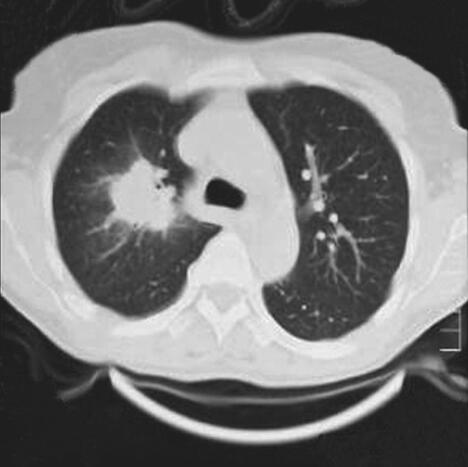

患者,女,52岁,新疆巴楚县农民,维吾尔族。因“间断发热6个月,发现肺部阴影和眼部肿物2个月”于2012年4月10日收入院。患者于6个月前出现间断发热,体温39~40.5℃,伴畏寒、寒战,持续30分钟至3小时可自行降至正常,发热时间间隔2~10天,曾于当地医院行胸片检查“未见明显异常”,给予“头孢类”抗生素治疗无效。2个月前出现双眼不适、右眼视力下降,眼科检查示“右眼肿物”,切除肿物病理示“少许坏死组织”。术前胸片检查发现“右肺上野圆形密度增高影”(图1);肺CT示“右肺上叶团块影,周围见分叶征,内见空洞;左肺下叶球形占位影,周围散在片状渗出影”(图2),遂于当地医院住院诊治。行支气管镜检查发现“右上叶肿物生长,各分支管腔狭窄,右中、下叶各支通畅;左支气管各支通畅”。行左下叶支气管刷检,病理报告“大片炎性渗出及坏死组织”。进而就左肺下叶病变行经皮肺穿刺活检术,病理报告“部分肺泡上皮增生,变性坏死组织炎性细胞浸润”。发热及肺部肿物诊断未明。患者因眼部肿物切除后出现右眼发红、疼痛、视力下降,10天前于我院眼科就诊,诊断为“右眼角膜穿孔、右眼眶蜂窝织炎”,行右眼摘除术,眼球病理示“中性粒细胞浸润,部分组织坏死伴脓性渗出物”。术后5天出现消化道大出血,肠镜示“结肠多发溃疡”,肠黏膜病理示“慢性炎症”,给予输血、止血治疗后出血停止。因发热和肺部肿物原因不明,为进一步诊治收入我科。近1个月患者发热呈持续性,体温39~40℃。10天前眼科术前复查胸片显示“右上叶不张”(图3);肺CT发现“右肺上叶阻塞性肺不张,左肺团块影,周围见片状渗出影”(图4)。患者发病以来,食欲不振、乏力明显,近半年体重下降5kg。

图2肺部CT

右肺上叶软组织肿块影;左肺下叶后基底段软组织影,边缘模糊